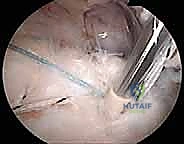

الخطوة 2: الاستكشاف بالمنظار (4K Arthroscopy)

يُحدث الدكتور هطيف 3 إلى 4 ثقوب صغيرة (بحجم ثقب المفتاح). يُدخل كاميرا دقيقة وعالية الوضوح (4K) لاستكشاف المفصل من الداخل. يتم تقييم حجم التمزق، جودة نسيج الوتر، والبحث عن أي إصابات مرافقة (مثل تمزق وتر البايسبس أو التهاب الجراب).

الخطوة 3: تنظيف وتجهيز العظم (Footprint Preparation)

لضمان التئام الوتر بالعظم، يجب إزالة الأنسجة الميتة والملتهبة. يقوم الجراح باستخدام أدوات دقيقة لكشط سطح العظم (Decortication) حتى يصل إلى العظم الإسفنجي الغني بالخلايا الجذعية والتروية الدموية، مما يحفز عملية الشفاء البيولوجي.

الخطوة 4: زراعة المثبتات وإصلاح مزدوج الصفوف

- الصف الداخلي: تُزرع مثبتات عظمية دقيقة (Anchors) محملة بخيوط جراحية فائقة القوة في الجزء الداخلي من البصمة العظمية.

- تمرير الخيوط: تُمرر هذه الخيوط عبر نسيج الوتر الممزق باستخدام أدوات دقيقة.

- الصف الخارجي: تُسحب الخيوط لتغطية الوتر فوق العظم، ثم تُثبت باستخدام مثبتات عظمية أخرى في الجزء الخارجي، مما يخلق شبكة محكمة تضغط الوتر بقوة ضد العظم.